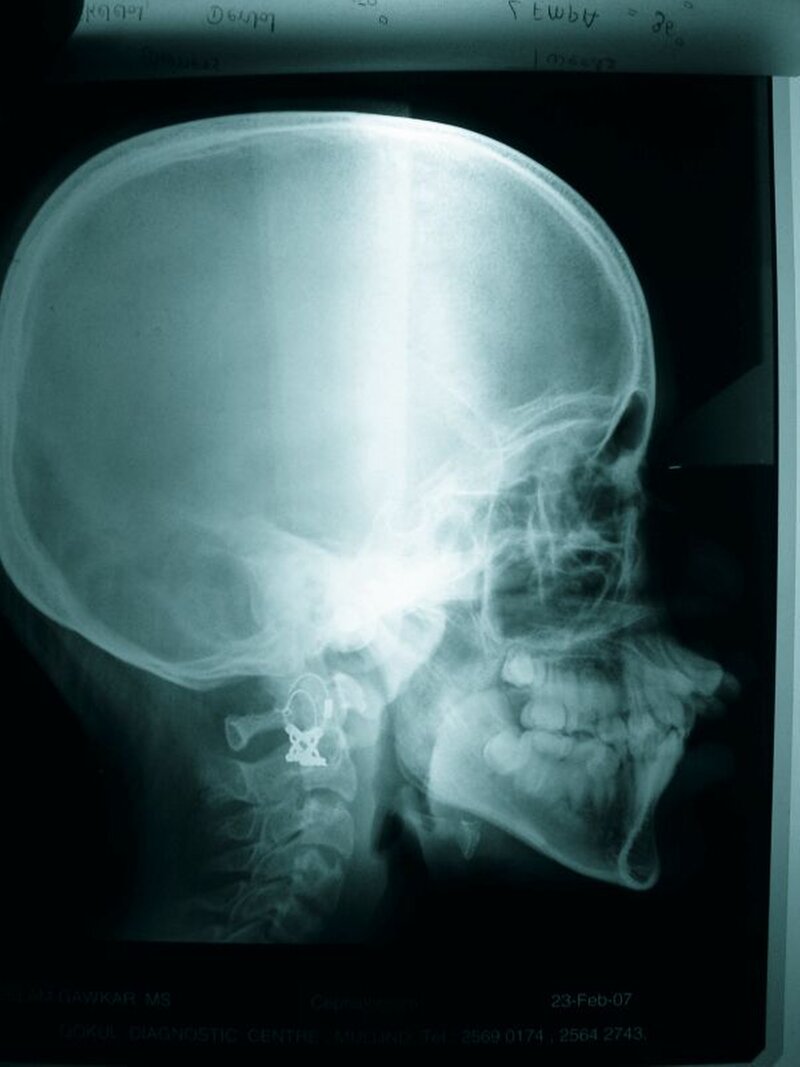

Die radiologische Untersuchung bestand aus einem Orthopantomogramm (OPTG), einer Aufbissaufnahme sowie einer Fernröntgenseitaufnahme (FRS). Neben der Übersicht der Gebissituation mit Nachweis des nicht durchgebrochenen Zahnes 22 im OPTG (Abbildung 3) war in der Aufbissaufnahme der Umfang der knöchernen Gaumenspalte klar zu erkennen (Abbildung 4). Das FRS ließ – bis auf die vertikal anterior verkürzte Maxilla und eine Protrusion der anterioren Prämaxilla – einen weitgehend normalen knöchernen Befund diagnostizieren (Abbildung 5).